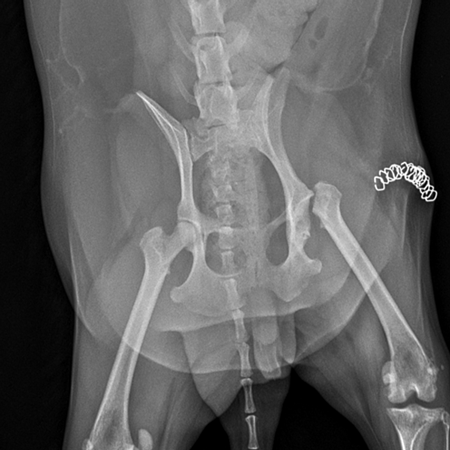

국내 최고 수준의 장비

Digital X-ray, 고해상도 초음파 등

진단 장비 갖추고 있으며

임상 경험이 풍부한 의료진이

직접 확인하고 치료 방향을 결정합니다.